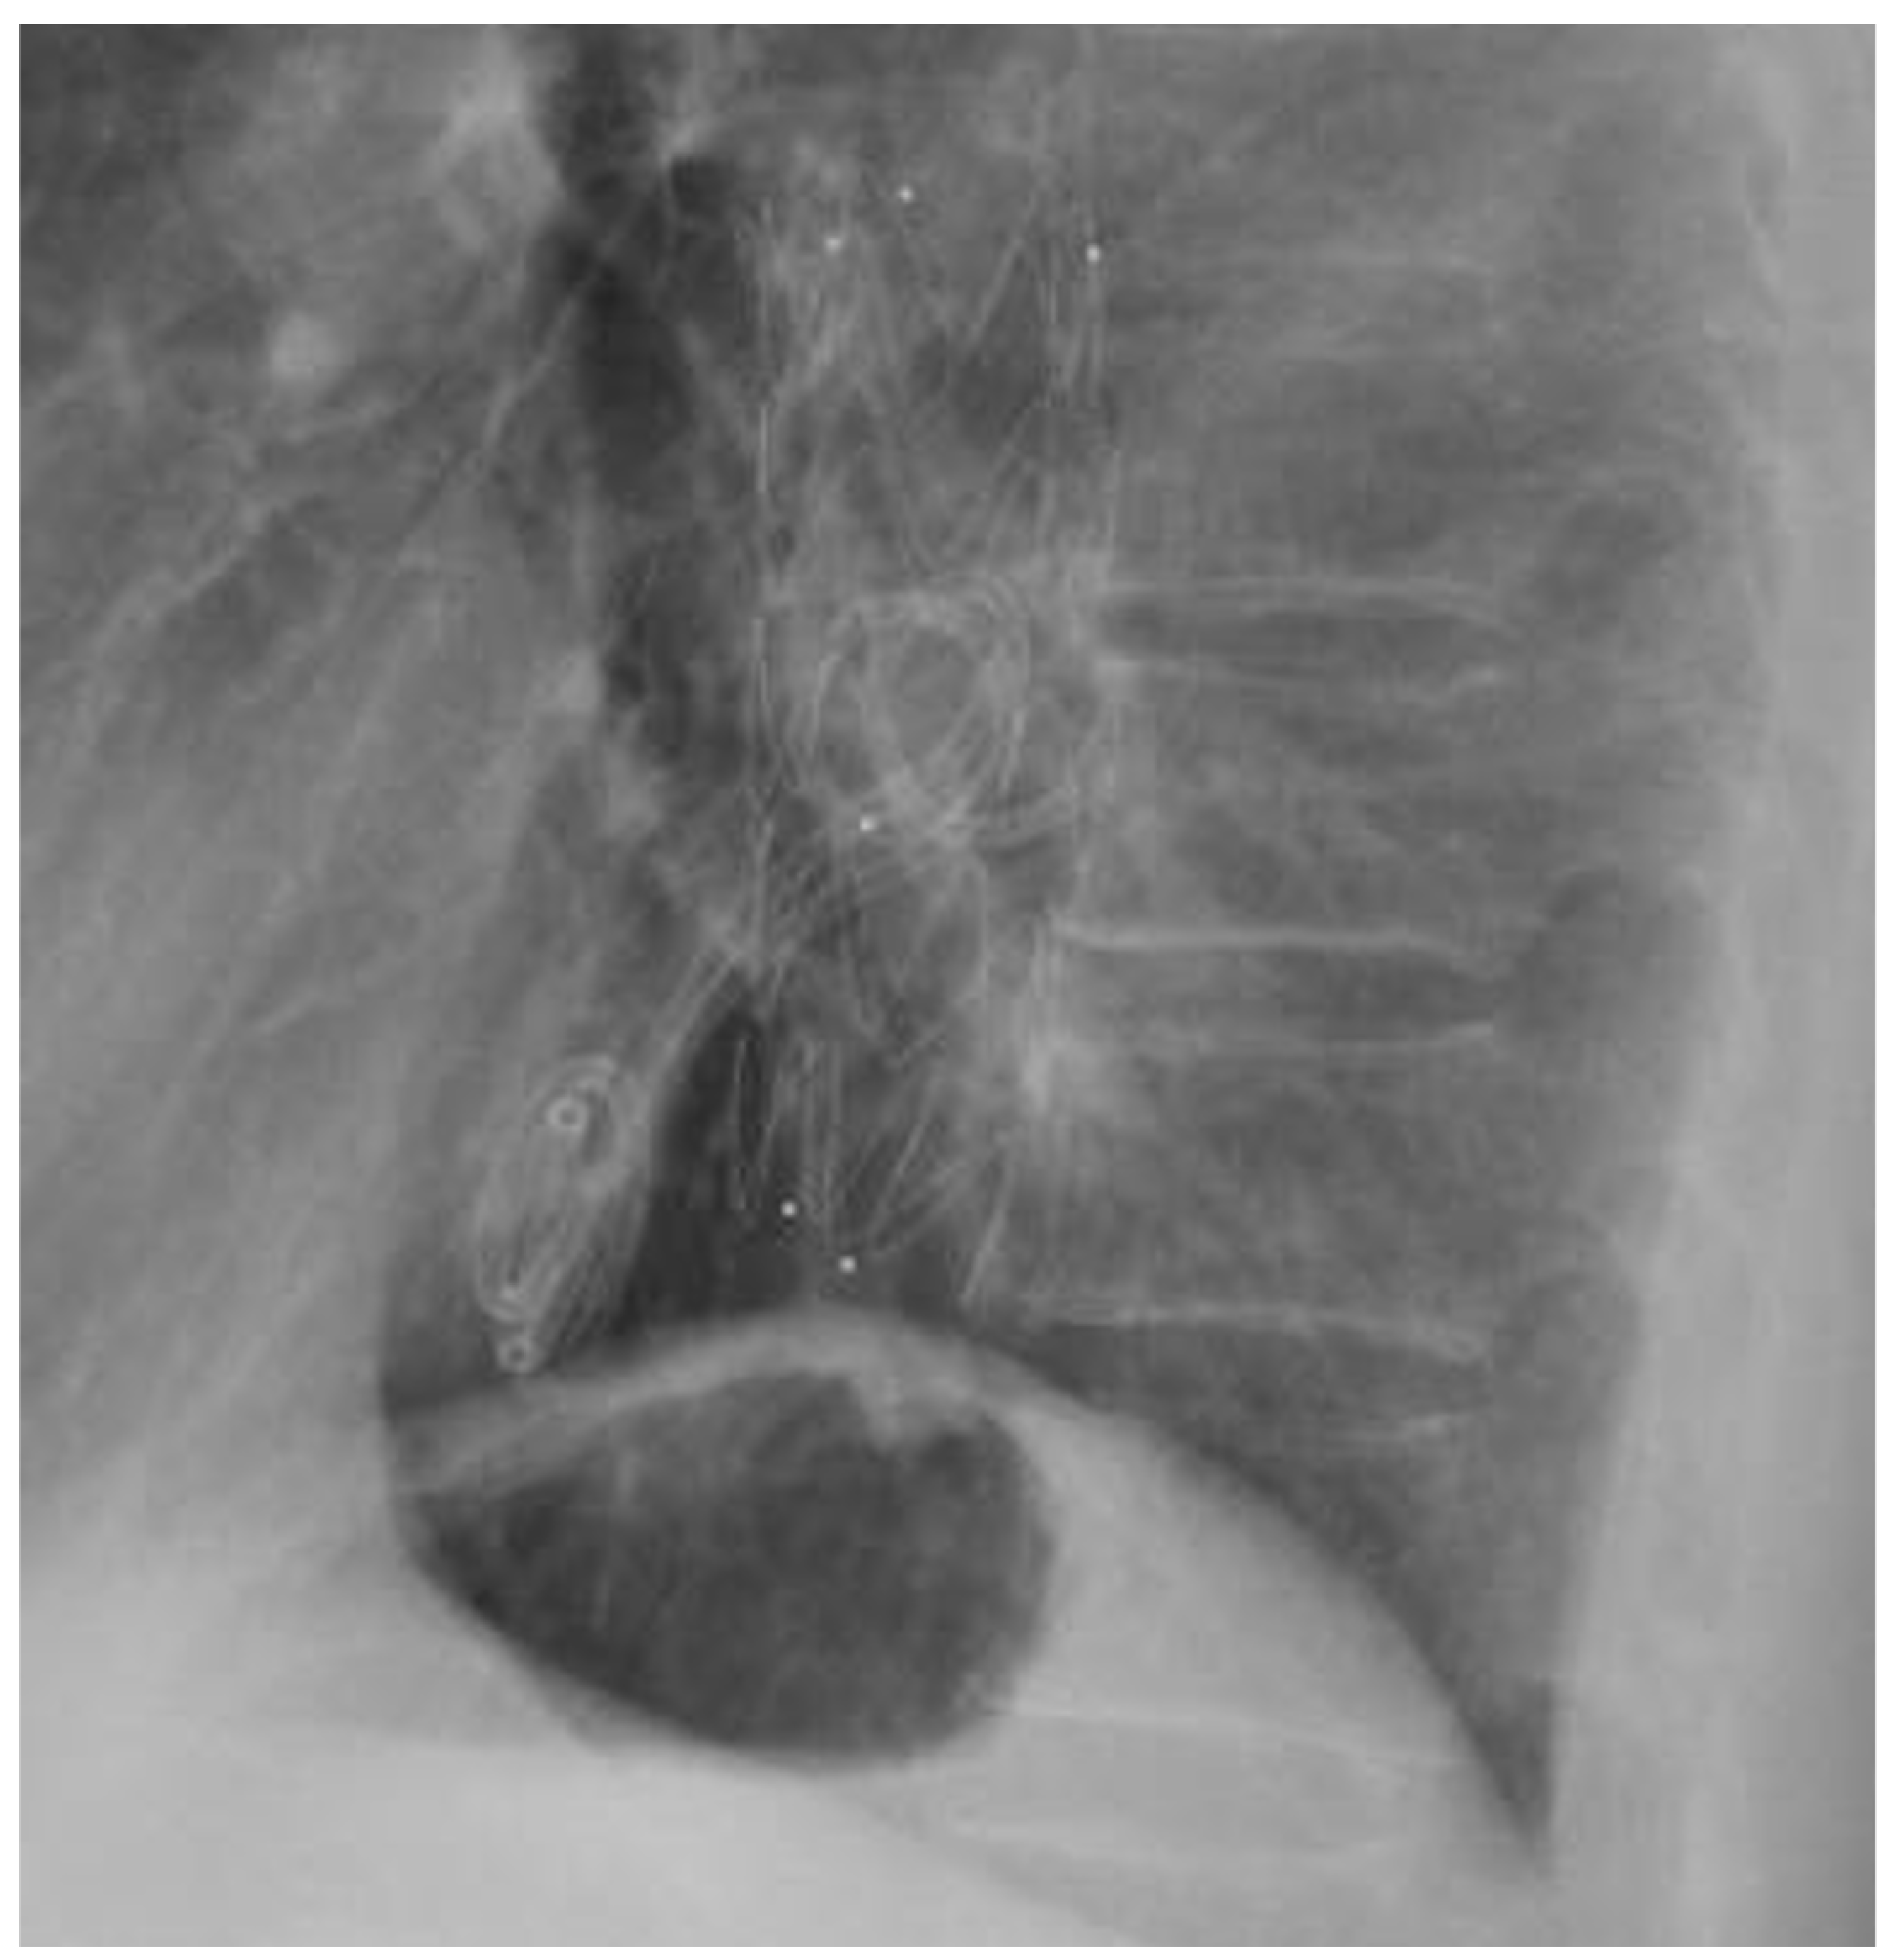

2.1. Case 1

2.2. Case 2